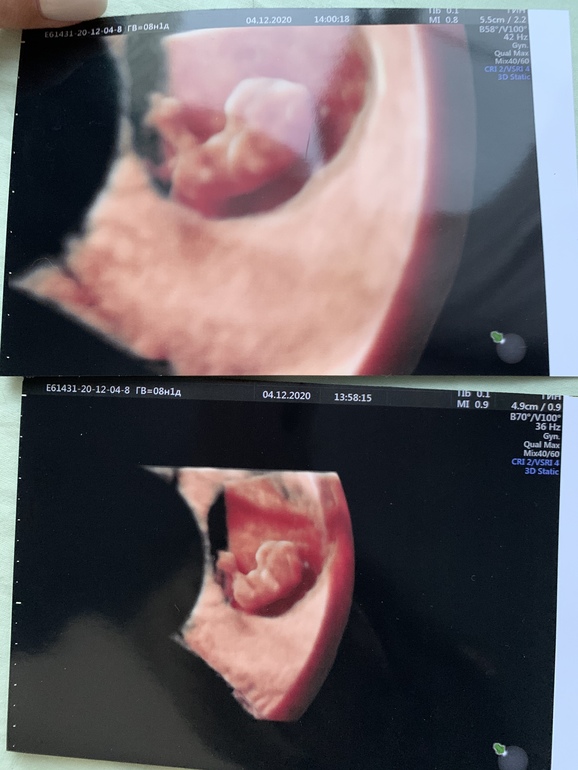

Узи делали и трансвагинально и абдоминально, честно говоря не знаю какая фотка откуда, не подскажите кто у нас будет?)